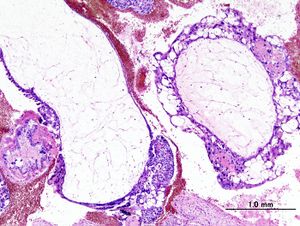

Histopathogic image of hydatidiform mole (complete type). H & E stain.